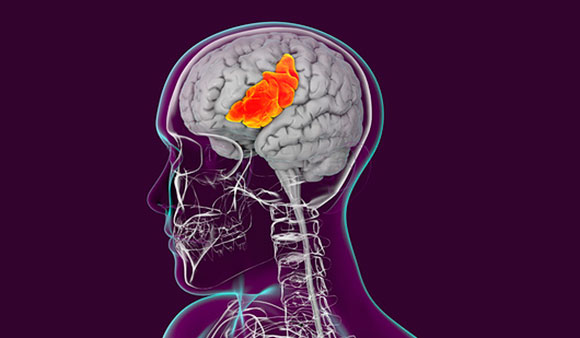

The human brain has areas that specialize in certain roles or enable specific abilities. For example, in the 19th century French physician, Paul Pierre Broca found that an area in the left side of the brain, currently named after him, plays a vital role in language formation. It was discovered that people with injuries to Broca's area suffer from aphasia: severe impairment in the ability to speak, which manifests as difficulty conjuring words and composing sentences with proper grammar. Damage to a nearby area in the left side of the brain, called Wernicke's area, causes a different type of aphasia This condition gained publicity recently when it was revealed that actor Bruce Willis suffers from it.

Nevertheless, understanding and forming language are highly complex activities that are not limited to Wernicke's and Broca's areas. Many parts of the brain participate in linguistic processing processes, and damage to any of them could result in impairments in speech, writing, or comprehending language. While a significant part of linguistic processing does occur in the left hemisphere, both hemispheres play a part in this processing to some extent.

The right hemisphere also specializes in certain functions. For example, the prefrontal cortex is essential for deciphering emotions in facial expressions. The right dorsal anterior cingulate cortex has been linked with the cerebral processing of music. However, these functions do not solely rely on the right hemisphere; both hemispheres are necessary to invoke a proper human response.

These distinctions led to the belief that artistically inclined individuals predominantly use their right brain, while analytical thinkers rely more on their left brain. In a 2013 study, researchers attempted to directly examine the claim that some people have one side of their brain stronger than the other. For this purpose they used fMRI to scan the brains of over one thousand subjects, aged 7-29, and examined their activity during rest. The findings did not present any evidence for the existence of a tendency for right or left brain dominance. While certain brain functions may be more related to a certain hemisphere, it is not sufficient to conclude that people have a dominant side to their brain.

In most people, areas important for language development are located in the left side of the brain. However, language processing, like many other complex functions, combines the activity of both hemispheres. Illustration of the part of the brain where Broca's area is located, which is important for language formation | Kateryna Kon. Science Photo Library